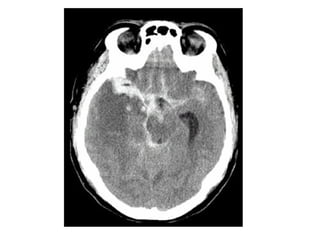

NECT shows hyperdense internal veins and bilateral (R > L) thalami

hypodensities , compatible with dural vein thrombosis and venous